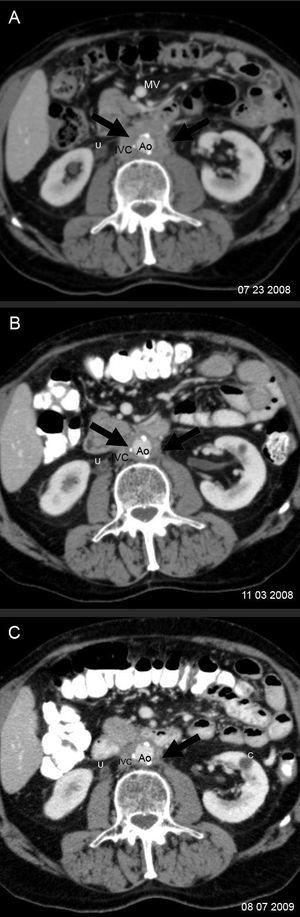

Diecinueve meses después de la cirugía, el paciente refirió un dolor lumbar de carácter sordo, edema bilateral de extremidades inferiores (+++), hidrocele bilateral y edema del pene. La ecotomografía abdominal mostró hidronefrosis derecha y una tomografía computarida de abdomen, un tejido periaórtico que comenzaba en la arteria mesentérica superior y envolvía a la aorta y a la vena cava inferior, extendiéndose hasta la bifurcación aórtica. Existían pequeñas adenopatías retroperitoneales. Los uréteres estaban libres hasta la vejiga. La imagen era indicativa de fibrosis retroperitoneal. El páncreas era radiológicamente normal (figura 1 y figura 2). Los exámenes de laboratorio mostraron anemia (Hto 35,2%, Hb 11,2 g/dl), VHS 50 mm/hora y creatinina 1,2 mg/dl. El recuento de glóbulos blancos fue 5.600 mm3, plaquetas 168.000 mm3, sedimento urinario normal, proteinuria 202 mg/24 horas, proteinemia 7,4 g/dl, albúmina 4,4 g/dl, globulinas 3,0 g/dl, uricemia 5,8 mg/dl, TSH 3,2 µU/l y APE 0,27 ng/ml. Con el diagnóstico clínico de fibrosis retroperitoneal idiopática se inició tratamiento con corticoides (deflazacort) 30 mg/día, colchicina 0,5 mg cada 12 horas y omeprazol 20 mg/día. Se eligió el deflazacort (DEF) por el antecedente de osteoporosis, dado su menor efecto sobre el metabolismo óseo. Un mes después el paciente estaba asintomático. Habían desaparecido el dolor lumbar, la anemia y el edema genital y de las extremidades inferiores. La VHS y la PCR se habían normalizado (8 mm/hora, <1 mg/l, respectivamente) y la función renal era normal. Se redujo el DEF a 22,5 mg/día, manteniendo la colchicina en 1 mg/día, enalapril, omeprazol, calcio y vitamina D. A los 2 meses de terapia se quejó de un leve dolor lumbosacro, había una discreta elevación de la VHS (18 mm/h) y de PCR (3,3 mg/l), por lo cual se aumentó el DEF a 30 mg/día. Al tercer mes estaba asintomático y la VHS y PCR se habían normalizado. Una tomografía computarida mostró una reducción del volumen del tejido retroperitoneal en un 25% (figura 2). Se redujo el DEF a 22,5 mg/dl manteniendo sin modificación los demás fármacos.

En los meses siguientes continuó asintomático y los exámenes de laboratorio no evidenciaron reactivación de la enfermedad, por lo que se redujo progresivamente la dosis de DEF hasta alcanzar los 6 mg cada 48 horas al año de iniciado el tratamiento, manteniendo la colchicina en 1 mg/día, que fue bien tolerada. La tomografía de control, efectuada a los 12 meses de iniciada la terapia, mostró desaparición de la hidronefrosis, reducción del volumen (33%) del tejido retroperitoneal (figura 2) y ausencia de alteraciones en el área pancreática. Los exámenes de laboratorio evidenciaron una función renal normal y ausencia de actividad inflamatoria o anemia. En el último control médico (a los 15 meses de iniciado el tratamiento), el paciente continuaba asintomático utilizando una dosis de mantenimiento de DEF de 6 mg en días alternos y colchicina 1 mg/día.

Figura 2. Control evolutivo de la fibrosis retroperitoneal con tomografía computarizada.